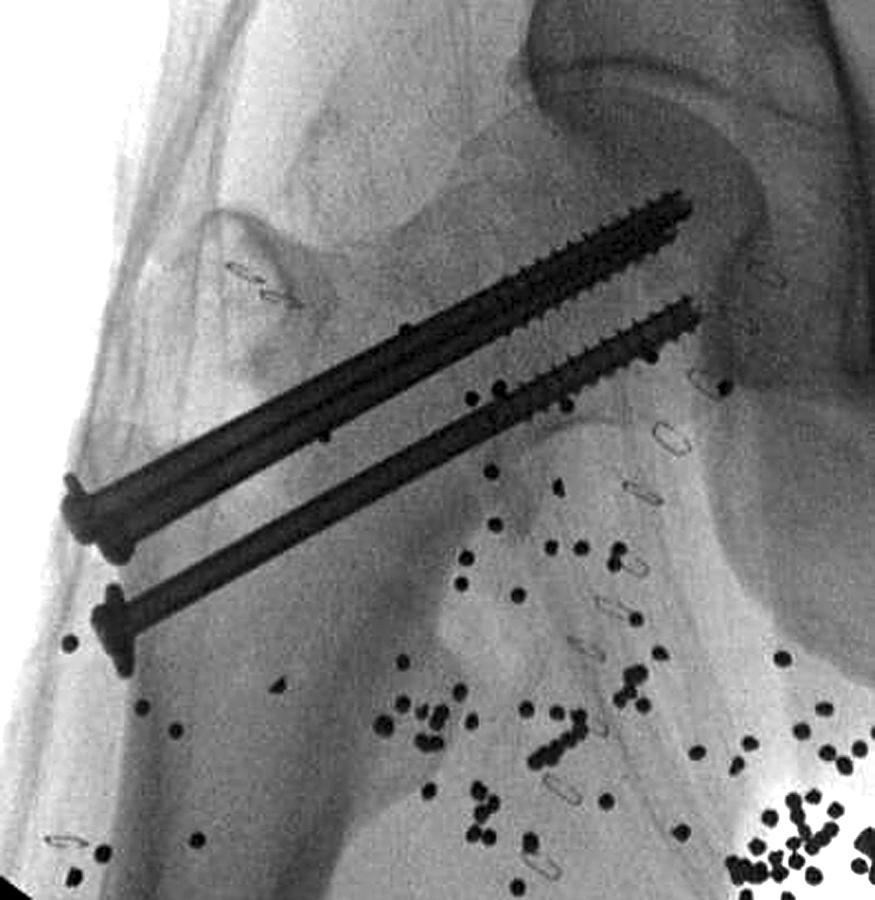

• We typically use three partially threaded screws (6.5, 7.0, or 7.3 mm) in an inverted triangle configuration ( Fig. 55.9A and B ).

FIGURE 55.9, For fixation of femoral neck fractures, three partially threaded screws can be inserted in an inverted triangle configuration (A and B) . Four screws can be placed in a diamond configuration when significant comminution is present (C) . ( SEE TECHNIQUE 55.1. )

Controversy exists about the best method of fixation for displaced subcapital and transcervical femoral neck fractures, and there are strong advocates of both cannulated screws ( Fig. 55.13 ) and compression hip screws . The recent FAITH (Fixation using Alternative Implants for the Treatment of Hip Fractures) randomized controlled trial showed no difference in reoperation rates between cancellous screws and SSP in the treatment of low-energy femoral neck fractures in patients older than 50 years. Subgroup analysis did suggest a potential advantage of SSP devices in displaced fractures, basicervical fractures, and in smokers, although there was a higher rate of osteonecrosis in patients treated with SSP devices (9% vs. 5%). Based on study protocol, none of the patients treated with SSP devices had supplemental fixation such as a derotational screw. Biomechanical studies suggest that a compression hip screw coupled with a derotational screw ( Fig. 55.14 ) is stronger than three cannulated screws in the treatment of unstable basicervical femoral neck fractures. A retrospective clinical study comparing fixation devices for Pauwels type III femoral neck fractures found no definitive evidence indicating the optimal fixation device. There was a higher nonunion rate with cannulated screws than with fixed angle devices (dynamic hip screw, cephalomedullary nail, dynamic condylar screw); however, this difference was not statistically significant. Biomechanical data suggest that a proximal femoral locking plate may be superior to both cannulated screws and a compression hip screw in a Pauwels type III femoral neck model, but clinical studies have not been encouraging. Berkes et al. reported a high incidence of catastrophic failure with proximal femoral locking plates. A different design of plate has shown improved results compared with cannulated screws; this design allows some controlled shortening. We typically reserve use of proximal femoral locking plates for fractures with significant femoral neck comminution ( Figs. 55.15 and 55.16 ). The Targon dynamic proximal femoral locking plate (Aesculap AG, Tuttlingen, Germany) ( Fig. 55.17A ), which has been used in Europe for more than a decade with generally favorable results, is currently not available in United States. The Conquest dynamic proximal femoral locking plate (Smith & Nephew, Memphis, TN) ( Fig. 55.17B ) is a similar option; however, clinical data currently are lacking.